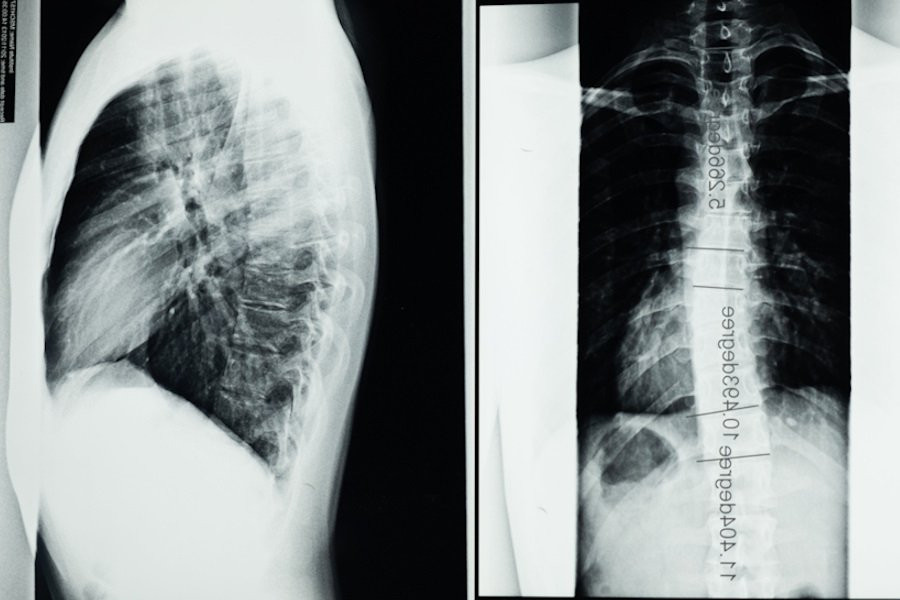

Методика, известная как функциональная ультразвуковая визуализация (fUSI), не только позволяет врачам визуализировать спинной мозг, но и отображать его реакцию на различные методы лечения в режиме реального времени. В исследовании, опубликованном сегодня в журнале Neuron, ученые подробно описывают, как fUSI воздействовал на шесть пациентов, получающих электростимуляцию для лечения хронической боли в спине.

Используя эту новую технологию, исследователи продемонстрировали интеграцию функциональных реакций спинного мозга на электрическую стимуляцию. Они отмечают, что гемодинамический ответ на стимуляцию отражает ранее не распознаваемую пространственно-временную модуляцию схемы спинного мозга. Это открытие предлагает новые возможности для оценки изменений кровотока с высоким уровнем пространственной и временной точности непосредственно в организме и демонстрирует потенциал фУЗИ в декодировании функционального состояния спинальных сетей. Этот прогресс имеет важное значение для дальнейшего развития методов изучения функции спинного мозга и эффектов клинической нейромодуляции.